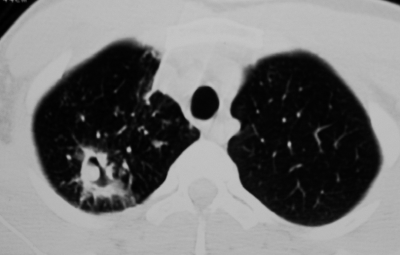

Рентгенологическая картина при туберкулёме зависит от типа и фазы развития. Чаще всего локализуется в I, II и VI сегментах лёгкого.

Затемнение при солитарной туберкулёме имеет округлую форму с чёткими и ровными контурами, средней интенсивности, при конгломератной — неправильную форму с полициклическим контуром. Контуры туберкулёмы обычно чёткие, однако их размытость указывает на перифокальную инфильтрацию, свидетельствующую о прогрессировании процесса. При этом могут наблюдаться пути к корню лёгкого в виде уплотнений по ходу сосудов и бронхов, а также очаги обсеменения. Негомогенность тени туберкулёмы объясняется неоднородностью казеозных масс: наличием фиброзных тяжей, кальцинатов и участков разрушения. В окружающей ткани часто выявляются немногочисленные полиморфные очаги и пневмофиброз[4][7].

При распаде туберкулёмы нередко образуется серповидная деструкция, расположенная у нижневнутреннего полюса. Также может появляться округлая или овальная полость в центральной части образования. В некоторых случаях распад сопровождается обильным выделением казеозных масс, что приводит к формированию каверны на месте туберкулёмы[6].